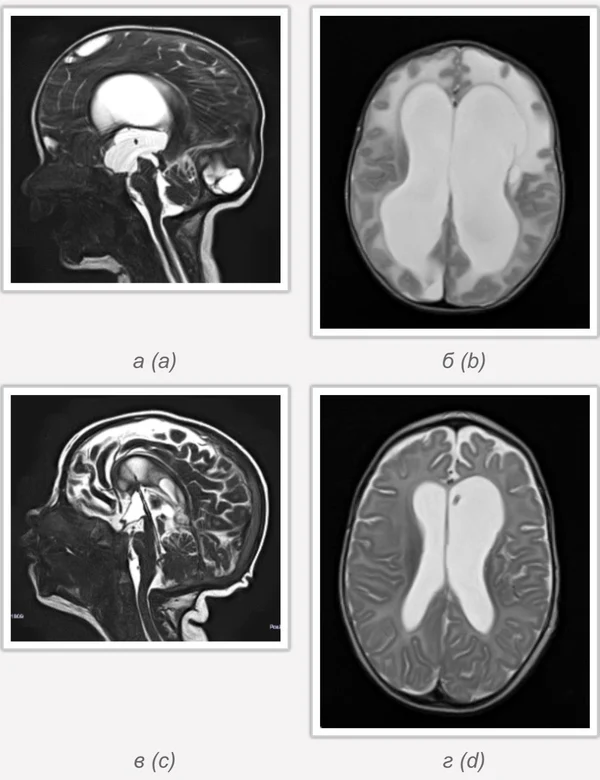

Гидроцефалия

Основной причиной гидроцефалии является окклюзия ликворных путей, встречающаяся у новорожденных детей в 60-70% случаев, к 3 годам частота окклюзионной гидроцефалии достигает 90%. Поэтому основной задачей лечения гидроцефалии являются устранение окклюзии ликворных путей, восстановление циркуляции ликвора и нормализация внутричерепного давления. В настоящее время эти задачи успешно позволяют решить эндоскопические методы хирургического лечения гидроцефалии. Эндоскопические операции проводятся нами во всех возрастных группах, включая недоношенных новорожденных детей, при разных локализациях и количествах окклюзий. При этом если эндоскопическая перфорация дна III желудочка (син.: эндоскопическая III-вентрикулостомия) малоэффективна у детей до 2-3-х летнего возраста, то новые методы эндоскопических операций, направленные на реканализацию естественных путей оттока ликвора с имплантацией стента (например эндоскопическая акведуктопластика, стентирование водопровода мозга) позволяют избежать имплантации шунтирующих систем у большинства пациентов с окклюзионными формами гидроцефалии. С целью снижение объема секреции ликвора и увеличения эффективности эндоскопических опеарций в некоторых случаях в комплексе с другими эндоскопическими операциями проводится эндоскопическая плексусэктомия. Операция заключается в коагуляции сосудистых сплетений боковых желудочков с последующим удалением их гломусных частей. Эндоскопические операции также проводятся при дисфункции ранее установленных шунтирующих систем у пациентов с окклюзионной гидроцефалией, что часто избавляет пациента от «шунт зависимости» и создает условия для удаления шунта. Имплантация ветрикулоперитонеальных, вентрикулоатриальных и др. шунтирующих систем нами применяется при сообщающейся форме гидроцефалии. У пациентов с окклюзионными формами гидроцефалии шунтирующие операции проводятся только при неэффективности ранее проведенных эндоскопических операций.